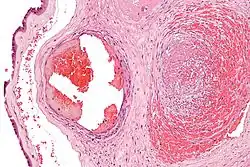

Fibrin (also called Factor Ia) is a fibrous, non-globular protein involved in the clotting of blood. It is formed by the action of the protease thrombin on fibrinogen, which causes it to polymerize. The polymerized fibrin, together with platelets, forms a hemostatic plug or clot over a wound site.

When the lining of a blood vessel is broken, platelets are attracted, forming a platelet plug. These platelets have thrombin receptors on their surfaces that bind serum thrombin molecules,[1] which in turn convert soluble fibrinogen in the serum into fibrin at the wound site. Fibrin forms long strands of tough insoluble protein that are bound to the platelets. Factor XIII completes the cross-linking of fibrin so that it hardens and contracts. The cross-linked fibrin forms a mesh atop the platelet plug that completes the clot. Fibrin was discovered[2] by Marcello Malpighi in 1666.[3]

Excessive generation of fibrin due to activation of the coagulation cascade leads to thrombosis, the blockage of a vessel by agglutination of red blood cells, platelets, polymerized fibrin and other components. Ineffective generation or premature lysis of fibrin increases the likelihood of a hemorrhage.